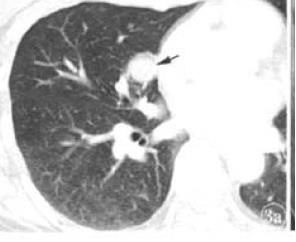

那下图是什么?

图2-3 胸部CT

绝对不能一看到新月征,就100%确定是曲霉菌感染。按原则办事,还要结合临床表现。上图患者未介绍有免疫力低下,没有发热、呼吸困难等症状,需鉴别肺硬化性血管瘤!